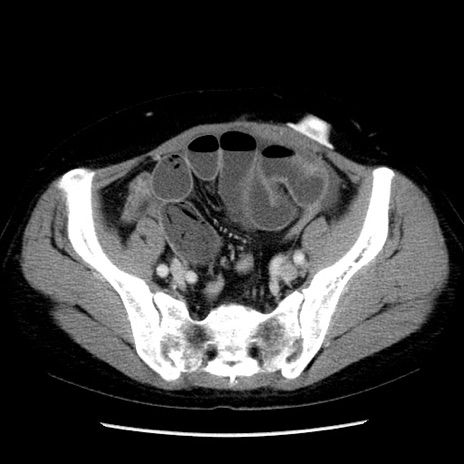

症例6(横断像)

【症例】50歳代女性

【主訴】下腹部痛

【現病歴】本日朝より下痢2回あり。 昼食を食べた後、嘔吐3回、下腹部痛認め、症状軽快せず、当院救急搬送。

最終食事:本日昼(生ものなし)。 昨日の夜、刺身を食ぺたとのこと。周囲に同様の症状の者なし。普段、排便は毎日あるとのこと。

【既往歴】卵巣癌術後(8年前に当院で卵巣摘出)

【身体所見】 意識清明、腹部:平坦、腸蠕動音→、やや硬、下腹部自発痛・圧痛あり、反跳痛あり、筋性防御なし。

【データ】WBC 16000、CRP 0.01